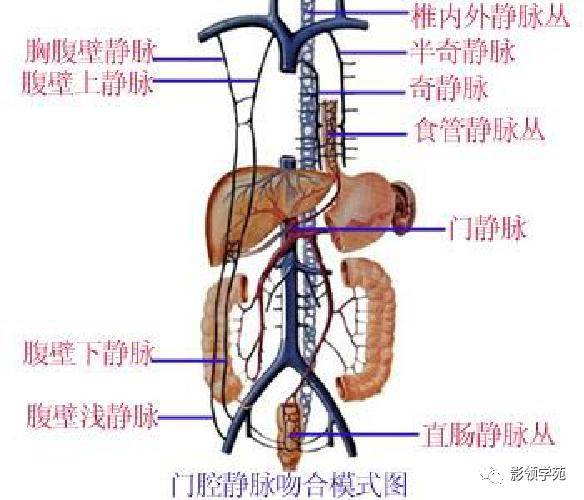

腹部动静脉

腹部动静脉